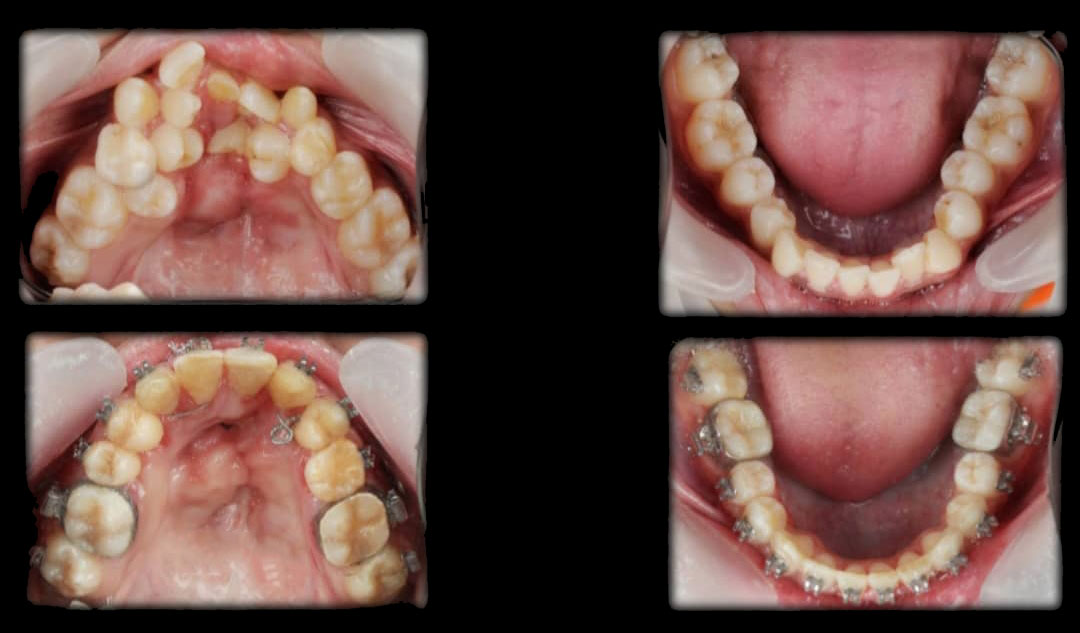

Braces are orthodontic appliances designed to correct crooked, crowded, or misaligned teeth, as well as bite issues such as overbite, underbite, or crossbite. By gently applying pressure, braces gradually move your teeth into proper alignment, improving both your smile and oral health.

Metal Braces

Traditional & reliable. These braces are strong, effective, and budget-friendly.